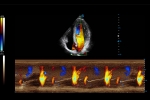

Oviduct 4D Ultrasound Angiography

Oviduct 4D contrast-enhanced ultrasound offers a safer and more effective way for intuitive visualization of oviduct in multiple angles. Great reproductivity in noninvasive operation enables treatment progress monitoring.

Auto EF

Cardiac function evaluation requires accuracy and speed as various calculations needs to be made. Auto EF, based on speckle tracking technology, acquires 2D EF and volumes within streamlined workflow.